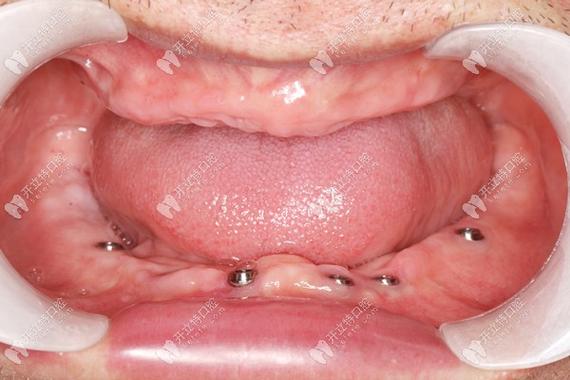

除传统种植体外,机构还提供All-on-4/6半口/全口即刻负重技术,仅需植入4-6颗种植体即可支撑半口牙桥,减少手术创伤,实现当天恢复咀嚼功能,为全口无牙患者带来福音。

李阿姨,72岁,全口牙缺失多年,戴活动义齿时常松动、疼痛,无法正常进食,检查发现牙槽骨严重吸收,医生采用All-on-4技术,植入4颗Nobel种植体支撑全口牙桥,当天佩戴临时义齿,3个月后更换永久氧化锆牙冠,李阿姨表示“现在能吃苹果、排骨,生活质量大大提高,整个人都年轻了”。